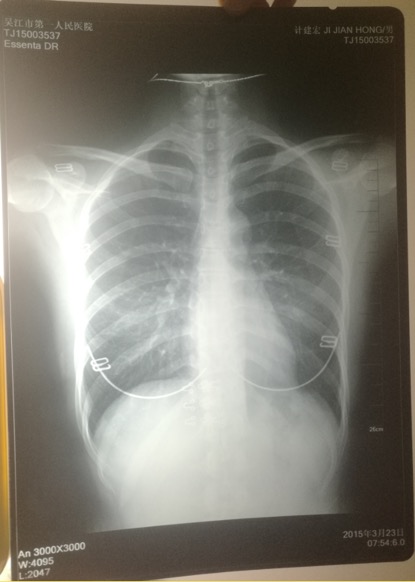

印有計建宏姓名的胸片實為一名女性的。 受訪者供圖

印著父親姓名的胸片,圖像卻顯示有明顯女性文胸搭扣和項鏈的印記。

“當時我和母親都奇怪,一年多前體檢正常,怎么這么快腫瘤長得如此大了?”更令計云強疑惑的是,該院胸外科主任在系統(tǒng)中輸入計建宏姓名后,查詢得到的胸片,可明顯看出有女性文胸的搭扣和項鏈,“后來醫(yī)生含糊地說可能是同名同姓,便不讓我看了。”

“7月初,我們回到吳江,帶著滿心悲傷和疑慮去了體檢科,想搞清楚父親的胸片究竟是怎么回事。”計云強稱,此后幾經(jīng)周折,在找了吳江區(qū)第一人民醫(yī)院體檢科、投訴科等多個部門后,耗時多月,才被體檢科通知去拿父親的胸片,“一張是我父親的名字,但有文胸印記;另一張是醫(yī)院所謂的我父親的胸片,顯示的是其他人的姓名。”